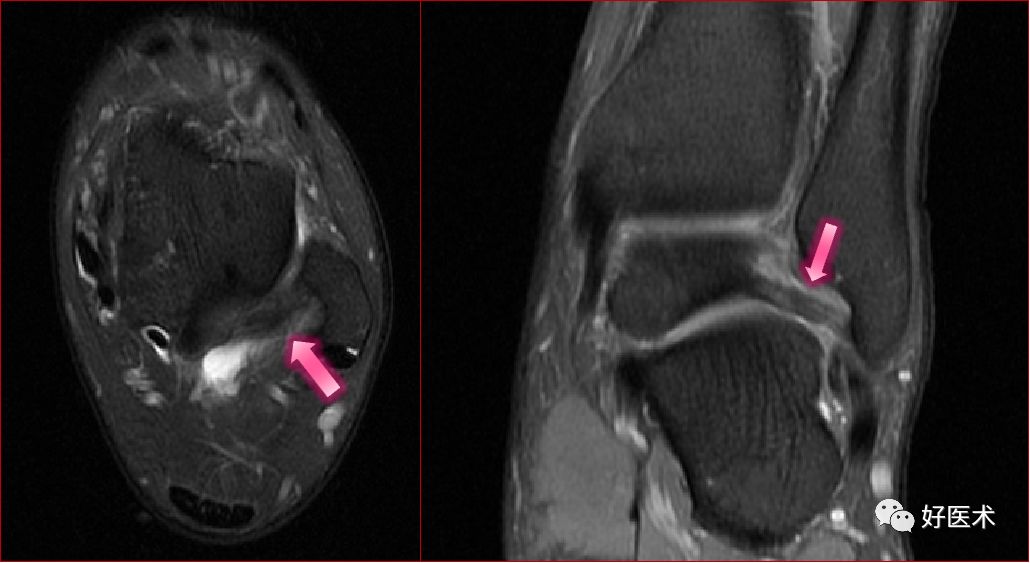

足底腱膜炎(跖腱膜炎)

足底腱膜炎MRI表现

足底腱膜炎:注意跟骨内侧结节的局限性水肿